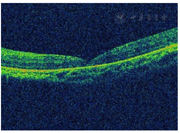

OCT检查:玻璃体及视网膜外层可见高反射团,黄斑区神经上皮层脱离(图3)。